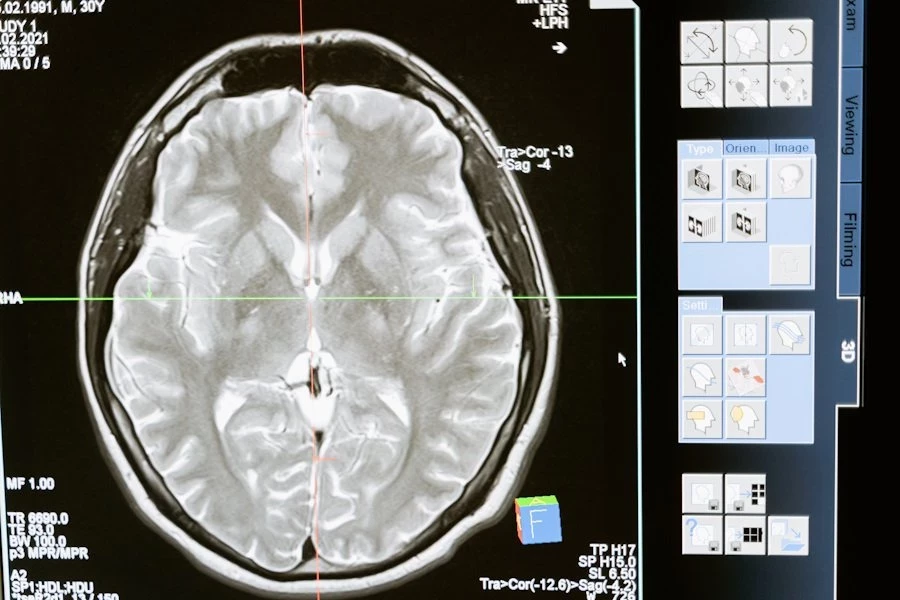

Транскраниальная магнитная стимуляция (TMS) — это метод медицинского исследования и терапии, который использует магнитные поля для воздействия на мозг человека. Этот метод немедленно и неинвазивно воздействует на активность мозга путем создания переменного магнитного поля над кожей головы.

Транскраниальная магнитная стимуляция используется в медицинских исследованиях для изучения функций мозга и их связи с различными психическими и нейрологическими состояниями, а так же для лечения некоторых болезней. Этот метод может помочь в восстановлении или модуляции активности мозга у пациентов с различными патологиями.